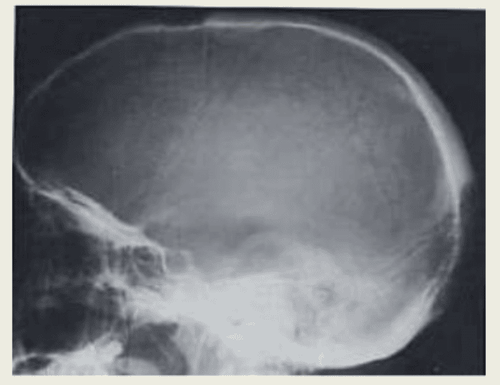

3.3 Chụp X-quang đầu

Chụp X-quang bao gồm việc cho một phần của cơ thể tiếp xúc với một liều lượng nhỏ bức xạ ion hóa để tạo ra hình ảnh bên trong cơ thể.